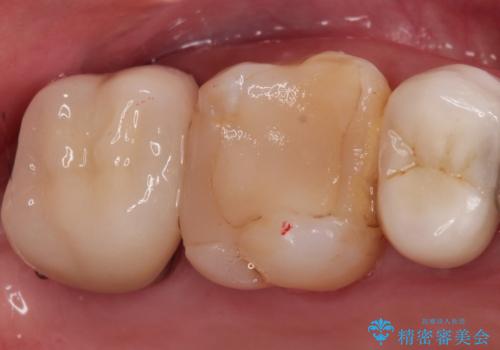

- 定期検診にて虫歯を見つけ、メタルボンドクラウンにて修復補綴治療を行なっております。

歯肉縁下まで虫歯が進行していたため歯周外科を併用して治療を行なっております。

メタルボンドクラウンは内側に金属のフレーム、外側にセラミックを使用した被せ物です。